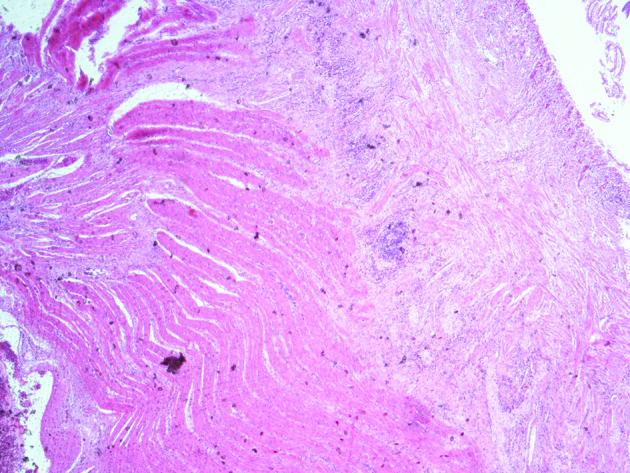

Ιστοπαθολογική εξέταση — Πολυοζώδης βρογχοκήλη (Ευγενική παραχώρηση Dr. V. Penopoulos)